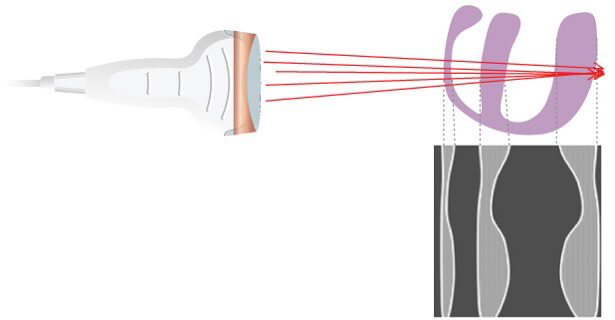

Scanning Technique

However, It is sufficient to perform a large number of different ultrasound shots by shifting the firing axis each time. The position of a point on the screen depends on the flight time of the echo and the position of the corresponding ultrasonic firing axis.

Sequence of Ultrasound Shots

Electronic Focusing and Beam-steering

Moving on to the electronic scanning technique, a subset of piezoelectric elements work together to produce the focused beam. Each of the transducers is excited with time offsets. The combination of several focal lengths at the emission improves the quality of the image.

Steering the Beam Electronically through the Scan Plane

The beam is electronically steered to scan a 2D plane.

Electronic Beam Focusing

The focusing of some transducers can be adjusted to a specific depth for each transmitted pulse. The transducer is made up of an array of several piezoelectric elements, rather than a single element compared to the fixed focus transducer. As shown in this animation, the elements are arranged in either a straight, or curved line in the linear array.

Focusing is achieved by not applying the electrical pulses to all of the transducer elements simultaneously. The pulse to each element is passed through an electronic delay The outermost elements will be pulsed first, which produces ultrasound that begins to move away from the transducer. The other elements are then pulsed in sequence, working toward the center of the array.

The centermost element will receive the last pulse. The pulses from the individual elements combine in a constructive manner, to create a curved composite pulse, which will converge on a focal point at some specific distance or depth from the transducer.

The focal depth is determined by the time delay between the electrical pulses. Focal Pulses can be changed electronically to give a good image detail at various depths within the body, rather than just one depth compared to the fixed focus transducer. One approach is to create an image by using a sequence of pulses, each one focused on a different depth or zone within the body.

Another approach is a group of piezoelectric elements that work together to produce the focused beam. Each of the transducers is excited with time offsets. The combination of several focal lengths on transmission improves the quality of the image. In return, the frame rate is decreased by a factor equal to the number of selected focal lengths. And last, the image is reconstructed by zone.